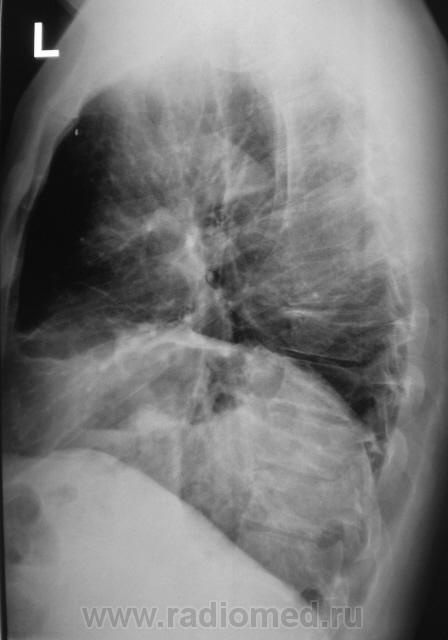

Рентгенограммы были сделаны в ургентном порядке, так как при поступлении, терапевта смутила стето-аускультативная картина слева.

Хотя, как выяснилось, жалоб пациент не предъявлял. Формальный диагноз при направлении на исследование -"Левосторонняя нижнедолевая пневмония". Произведена стандартная рентгенография в двух проекциях (без врача).

Возник извечный вопрос - пневмония, ателектаз, базальный плеврит.

А если ограничится банальной релаксацией купола диафрагмы и "нехай живе" как говорят у нас....?

Вот эта "газовая структура" очень меня смутила, да еще и пациент, который, оказывается жалоб никаких не предъявляет.

Такая релаксация левого купола дала бы хорошую одышку. И такие жалобы должны быть постоянны.

Знаете, когда слева релаксация, тогда, как правило, наступают неполные завороты (или повороты) желудка вокруг горизонтальной оси, при этом газовый пузырь приобретает весьма и весьма замысловатую, как правило вытянутую по горизонтали и спереди-назад форму. Почему бы этому и не быть?